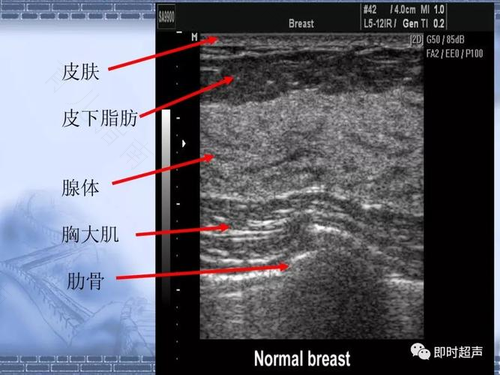

通常女性在做乳腺B超检查时,要是B超影像显示腺体厚度不超过0.8cm的话,那就是乳腺腺体比较薄的情况。因为正常女性的乳腺厚度应该在0.8到1.2之间。有时候会受一些外界因素的影响,而出现腺体增厚或是腺体变薄的情况。